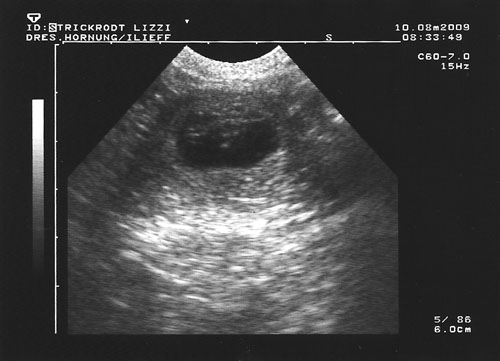

Lizzy wird Mama! Der Ultraschall hat es ans Licht gebracht, unsere weite Reise war erfolgreich!